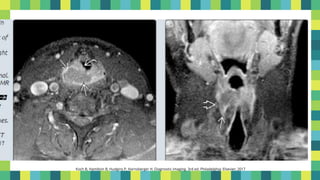

14

Koch B, Hamilton B, Hudgins P, Harnsberger H. Diagnostic imaging. 3rd ed. Philadelphia: Elsevier; 2017